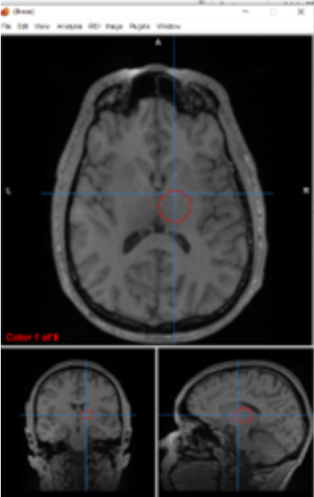

thalamus

filters information, regulates conscoiusness and sleep

basal ganglia/thalamus

motor control